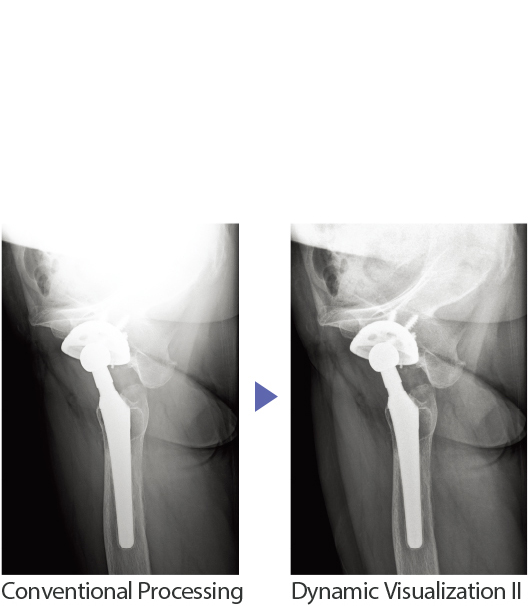

Dynamic Visualization II

Image quality using advanced exposure recognition algorithms

Fujifilm’s original algorithms automatically adjust contrast and density for individual body parts based on calculation of estimated 3D image data.

Improved control of the density and contrast in areas with overlapping tissue provides clearer observation.

Improved detection and display of the Skin edge and outline of lumber spine in patients with increased thickness.

In this spinal image, by suppressing black-out and white-out in the image, the alignment of the entire vertebral column and spinal kyphosis is greater visualized.